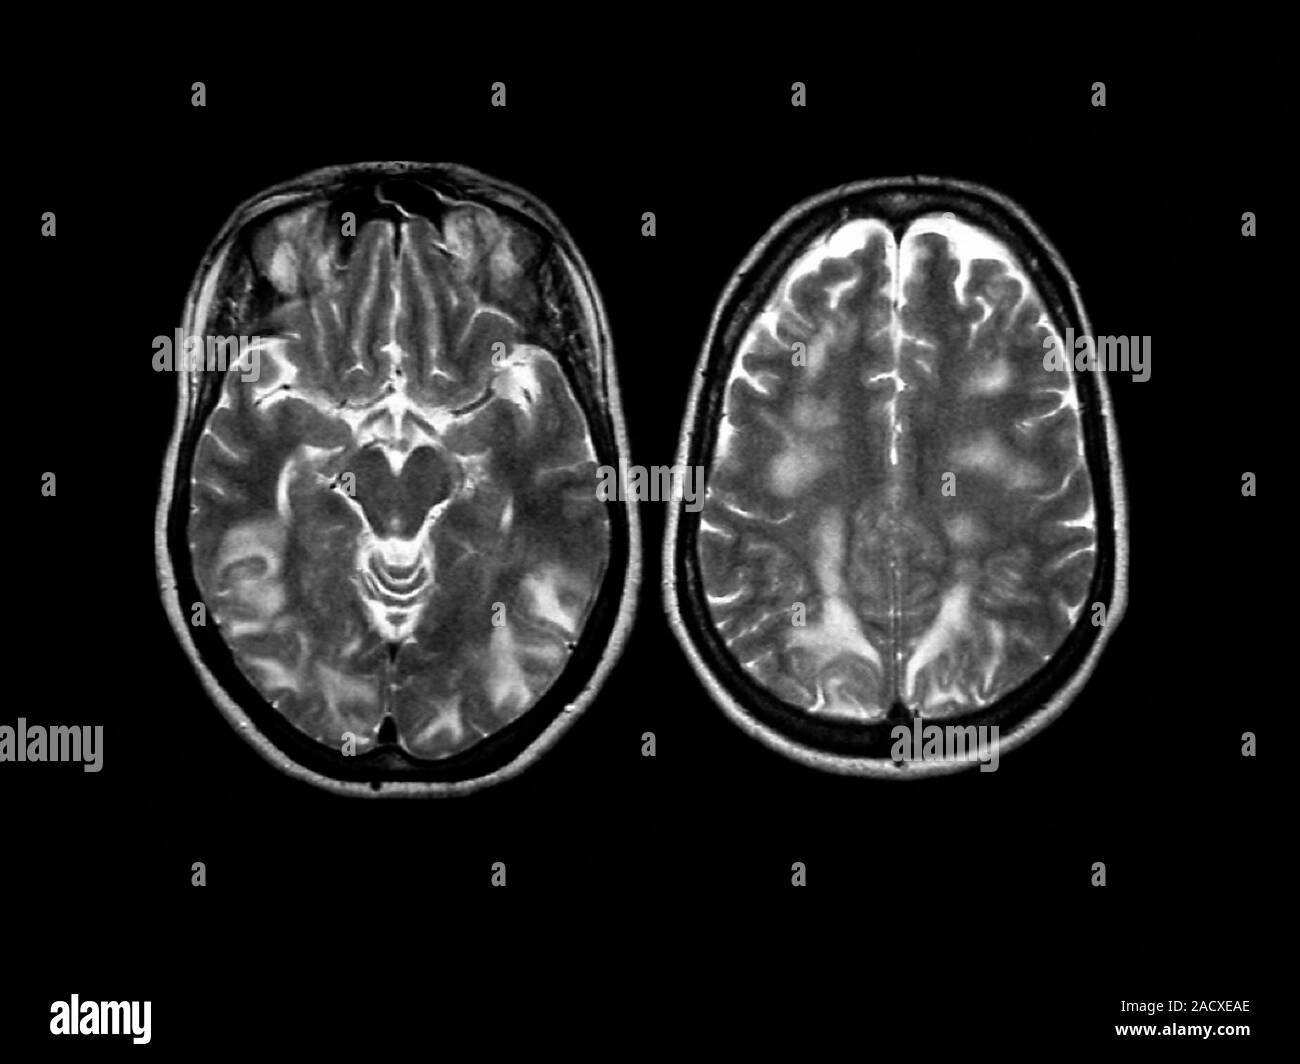

From www.alamy.com

Eclampsia. resonance imaging (MRI) scan of the brain of a 27 year old woman (from below Eclampsia Radiology E levated l iver enzymes and. Preeclampsia, defined as the new onset of hypertension, peripheral edema, and proteinuria after at least 20 weeks of gestation in a woman previously without. We assessed the distribution and. Posterior reversible encephalopathy syndrome is associated with eclampsia. Clinical and neuroradiographic correlates and insights into the pathogenesis. It is considered a severe and life. Eclampsia Radiology.

Eclampsia. resonance imaging (MRI) scan of the brain of a 27 year old woman (from below Eclampsia Radiology Clinical and neuroradiographic correlates and insights into the pathogenesis. Posterior reversible encephalopathy syndrome is associated with eclampsia. Preeclampsia, defined as the new onset of hypertension, peripheral edema, and proteinuria after at least 20 weeks of gestation in a woman previously without. E levated l iver enzymes and. We assessed the distribution and. It is considered a severe and life. Eclampsia Radiology.